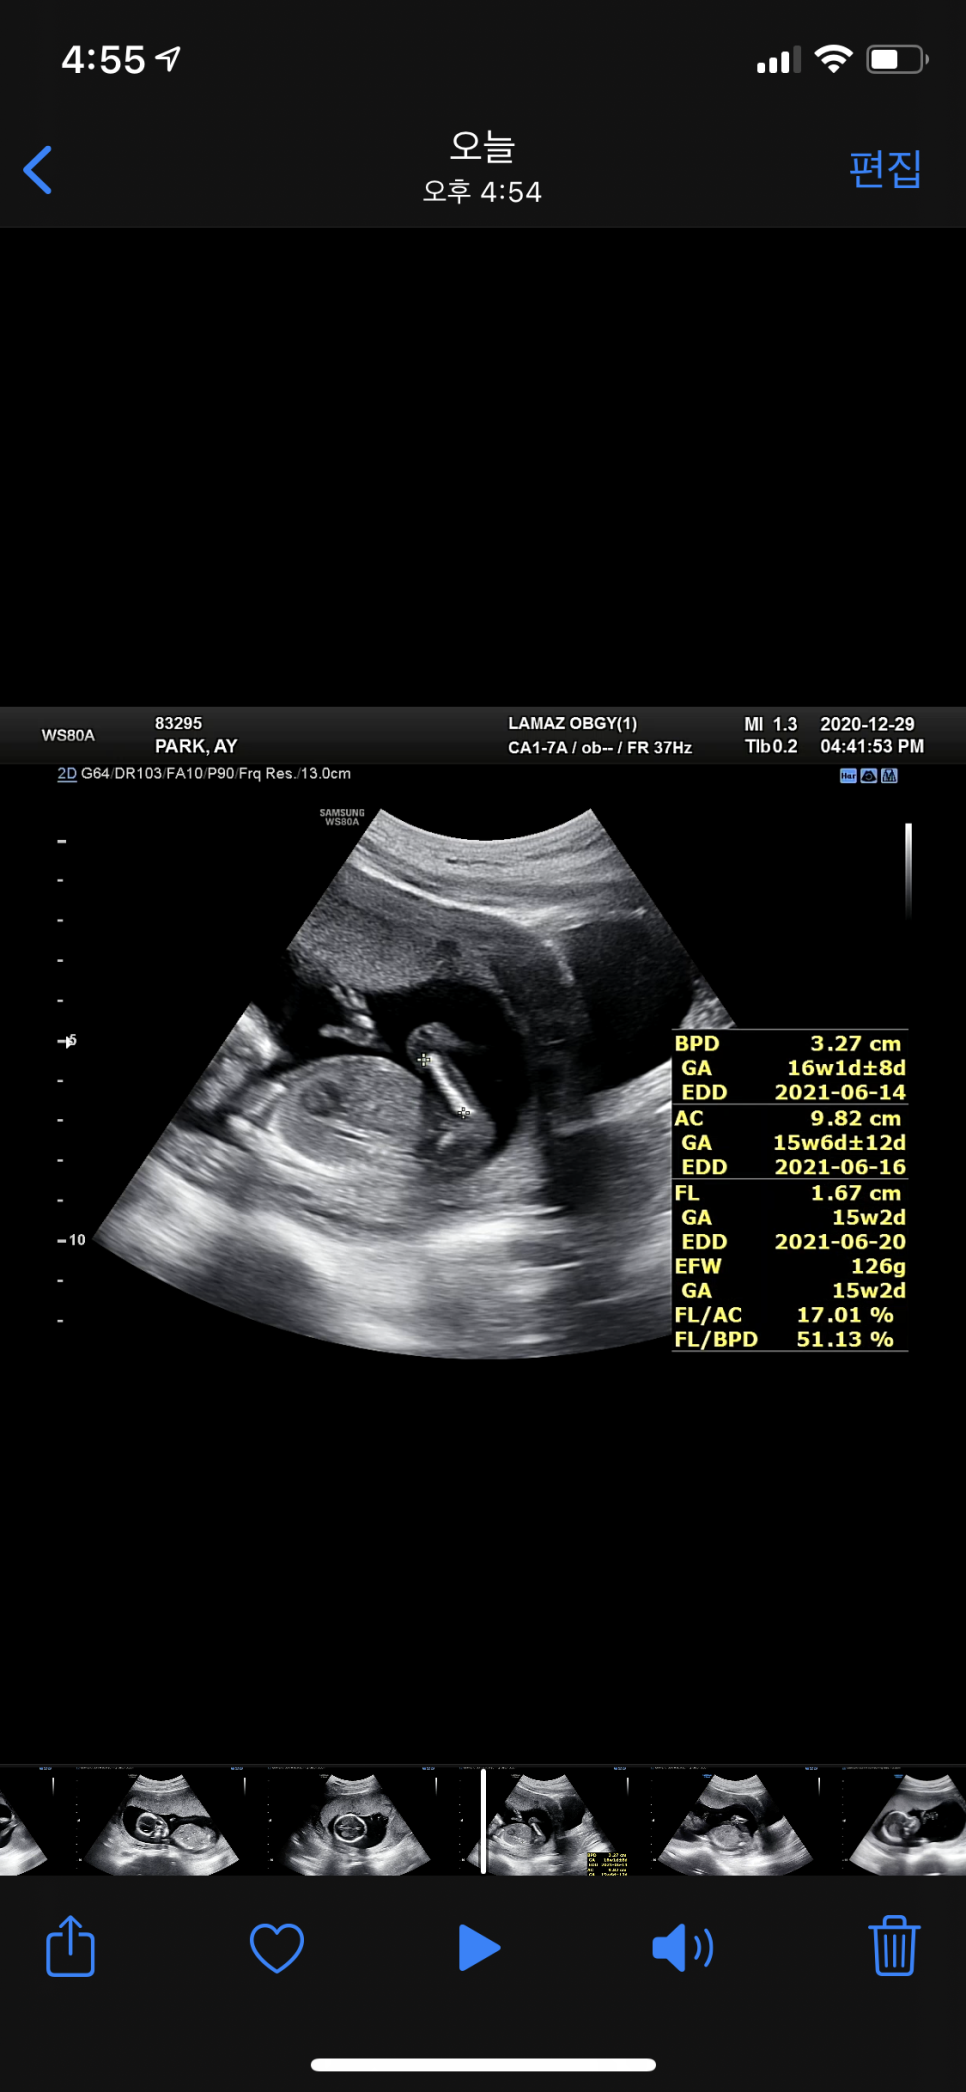

임신 16주 초음파

이 시기의 평균 아가 길이는 11-13cm / 60-120g

우리 별똥별은? 13.2cm / 126g

건강 그 자체입니다 ㅎㅎ

- 2차 기형아 검사를 실시하는(원한다면 취약x증후군 검사를 함께 실시할 수 있다) 태아의 성별이 나오는 시기 척추, 손가락, 발가락, 뼈 모두 완성되는 시기·태아의 급격한 성장과 더불어 빈혈이 일어나기 쉬우므로 ‘철분’ 필수섭취 태아의 뼈형성에 필요한 ‘칼슘’의 보충도 확보 태아 평균 신장 11-13cm, 60-120g-16주 초음파로 간주하는 큰 이상이 없으면 안정기가 된다.·조금 격렬한 운동을 해도 좋은 시기·신체뿐만 아니라 뇌의 발달도 현저하게 뇌의 ‘해마’ 발달 개시.청각과 기억능력이 시작되므로 태교를 시작하면 좋은 자극이 된다.